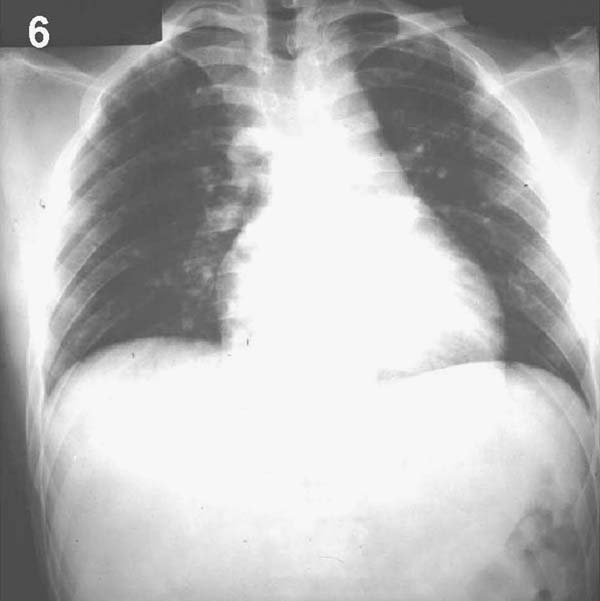

Placa 6